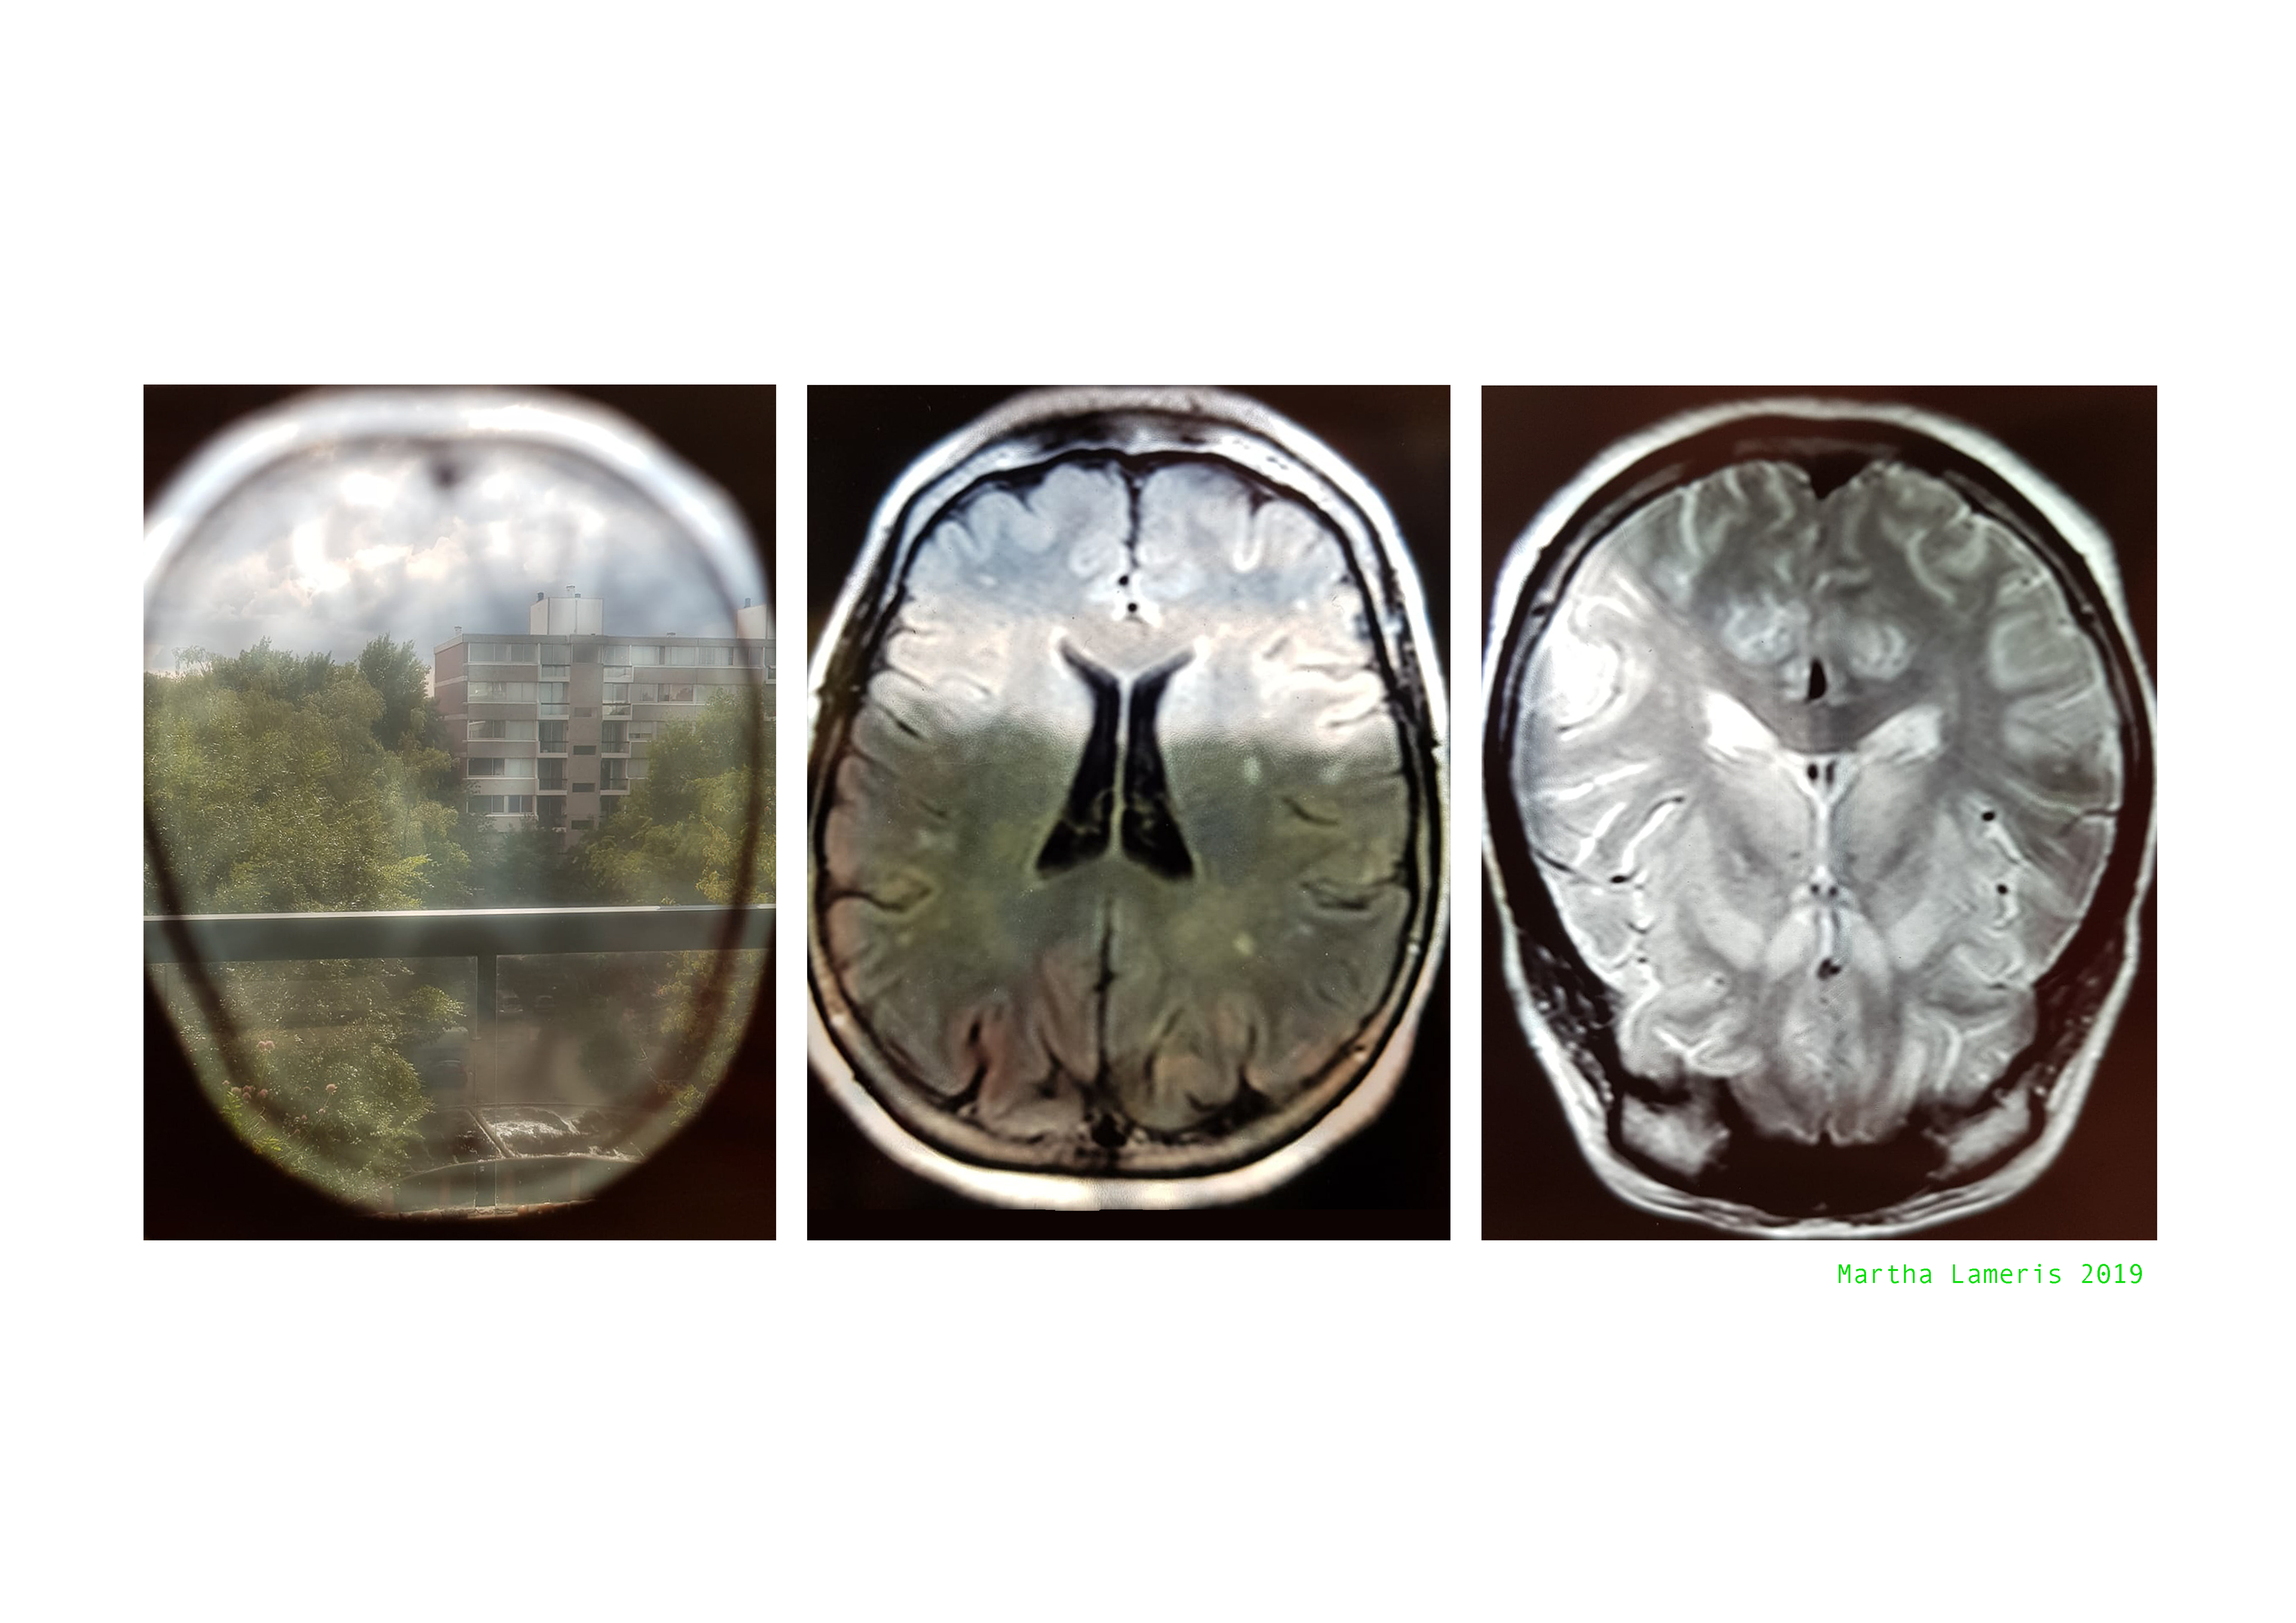

Foto's door Annette van der Goes, Amsterdam MS Centrum

Van Links naar rechts: Martha Lameris, Iris Jousma, Andrea van Sloterdijck en Lisette Oliemeulen 2019